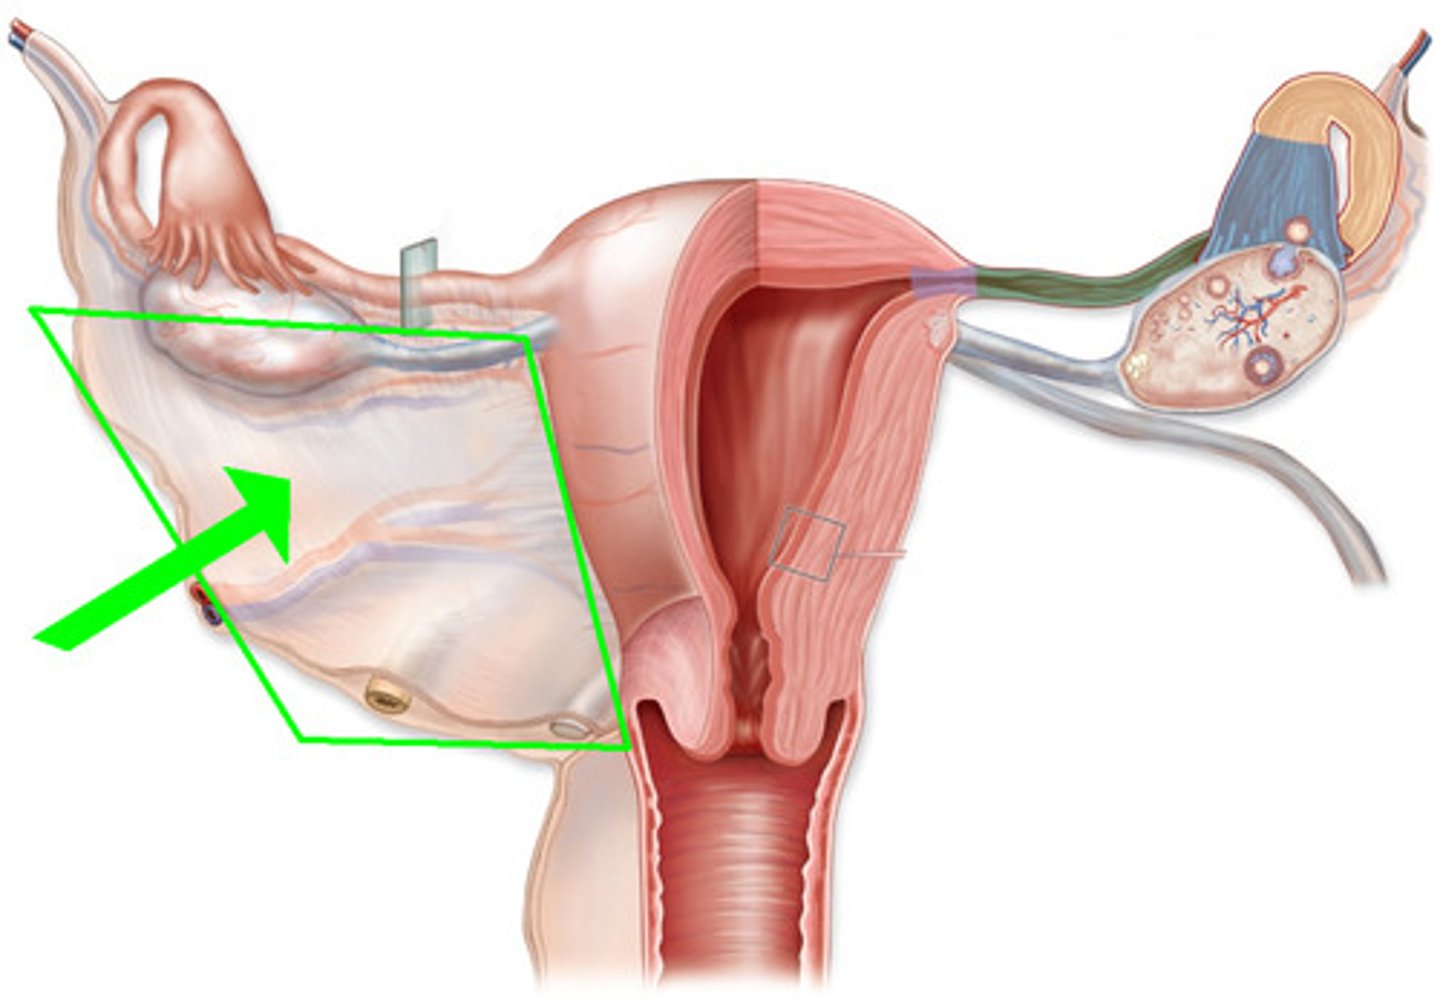

uterine (fallopian) tubes

accessory ducts of the female reproductive system

broad ligament

ligament that hands like a tent from the uterus and uterine tubes

suspensory ligament of ovary

Ligament that contains ovarian vessels

ovarian ligament

ligament that attaches ovary to uterus

uterine tubes (fallopian tubes)

function: receive the ovulated oocyte and provide a site for fertilization

tube extends from an ovary laterally and to the uterus medially

fimbriae

Fingerlike projection of the uterin (fallopian) tubes that drape over the ovary.